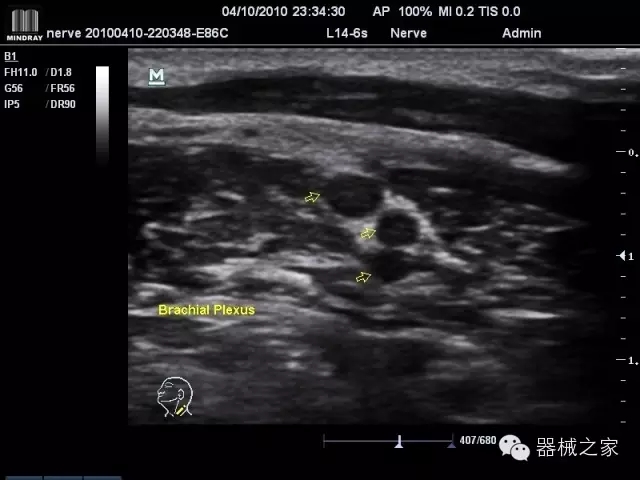

臨床圖片賞析

產(chǎn)品特點